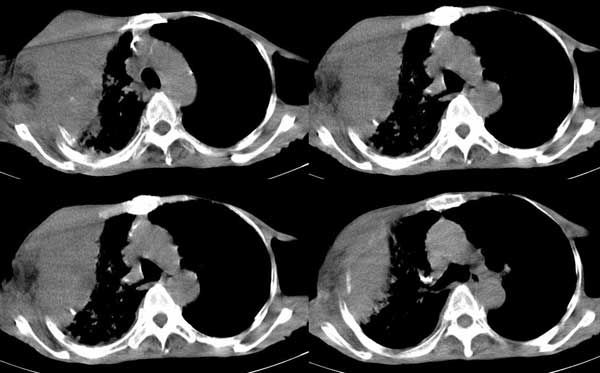

右侧胸廓塌陷。右前上外侧胸壁软组织肿块,其内见有低密度影,肋骨呈溶骨性表现。右肺上叶见大量的间质纤维化表现。右侧膈肌上抬。

肺尖巨大肿块影阴,胸壁受侵肋骨破坏,肿块密度不均且穿破胸壁入皮下,应该是:肺上沟癌;由于肺内有斑片状播散病灶,因此不排除胸壁结核。

我觉得这个人右侧胸部的肿块来源于肋骨或胸壁软组织,从病灶的形态来和最大直径来看,来源于肋骨的可能更大,可以基本定性为恶性。

考虑:1 右侧胸壁恶性肿瘤(多考虑:胸膜间皮瘤)。

2 继发性结核,右结核性胸膜炎伴胸壁结核性感染。

考虑右侧胸壁恶性肿瘤伴右肺癌性淋巴管炎 (肺上沟瘤常有神经方面的症状,结核如此严重无明显结核中毒症状也很少见)